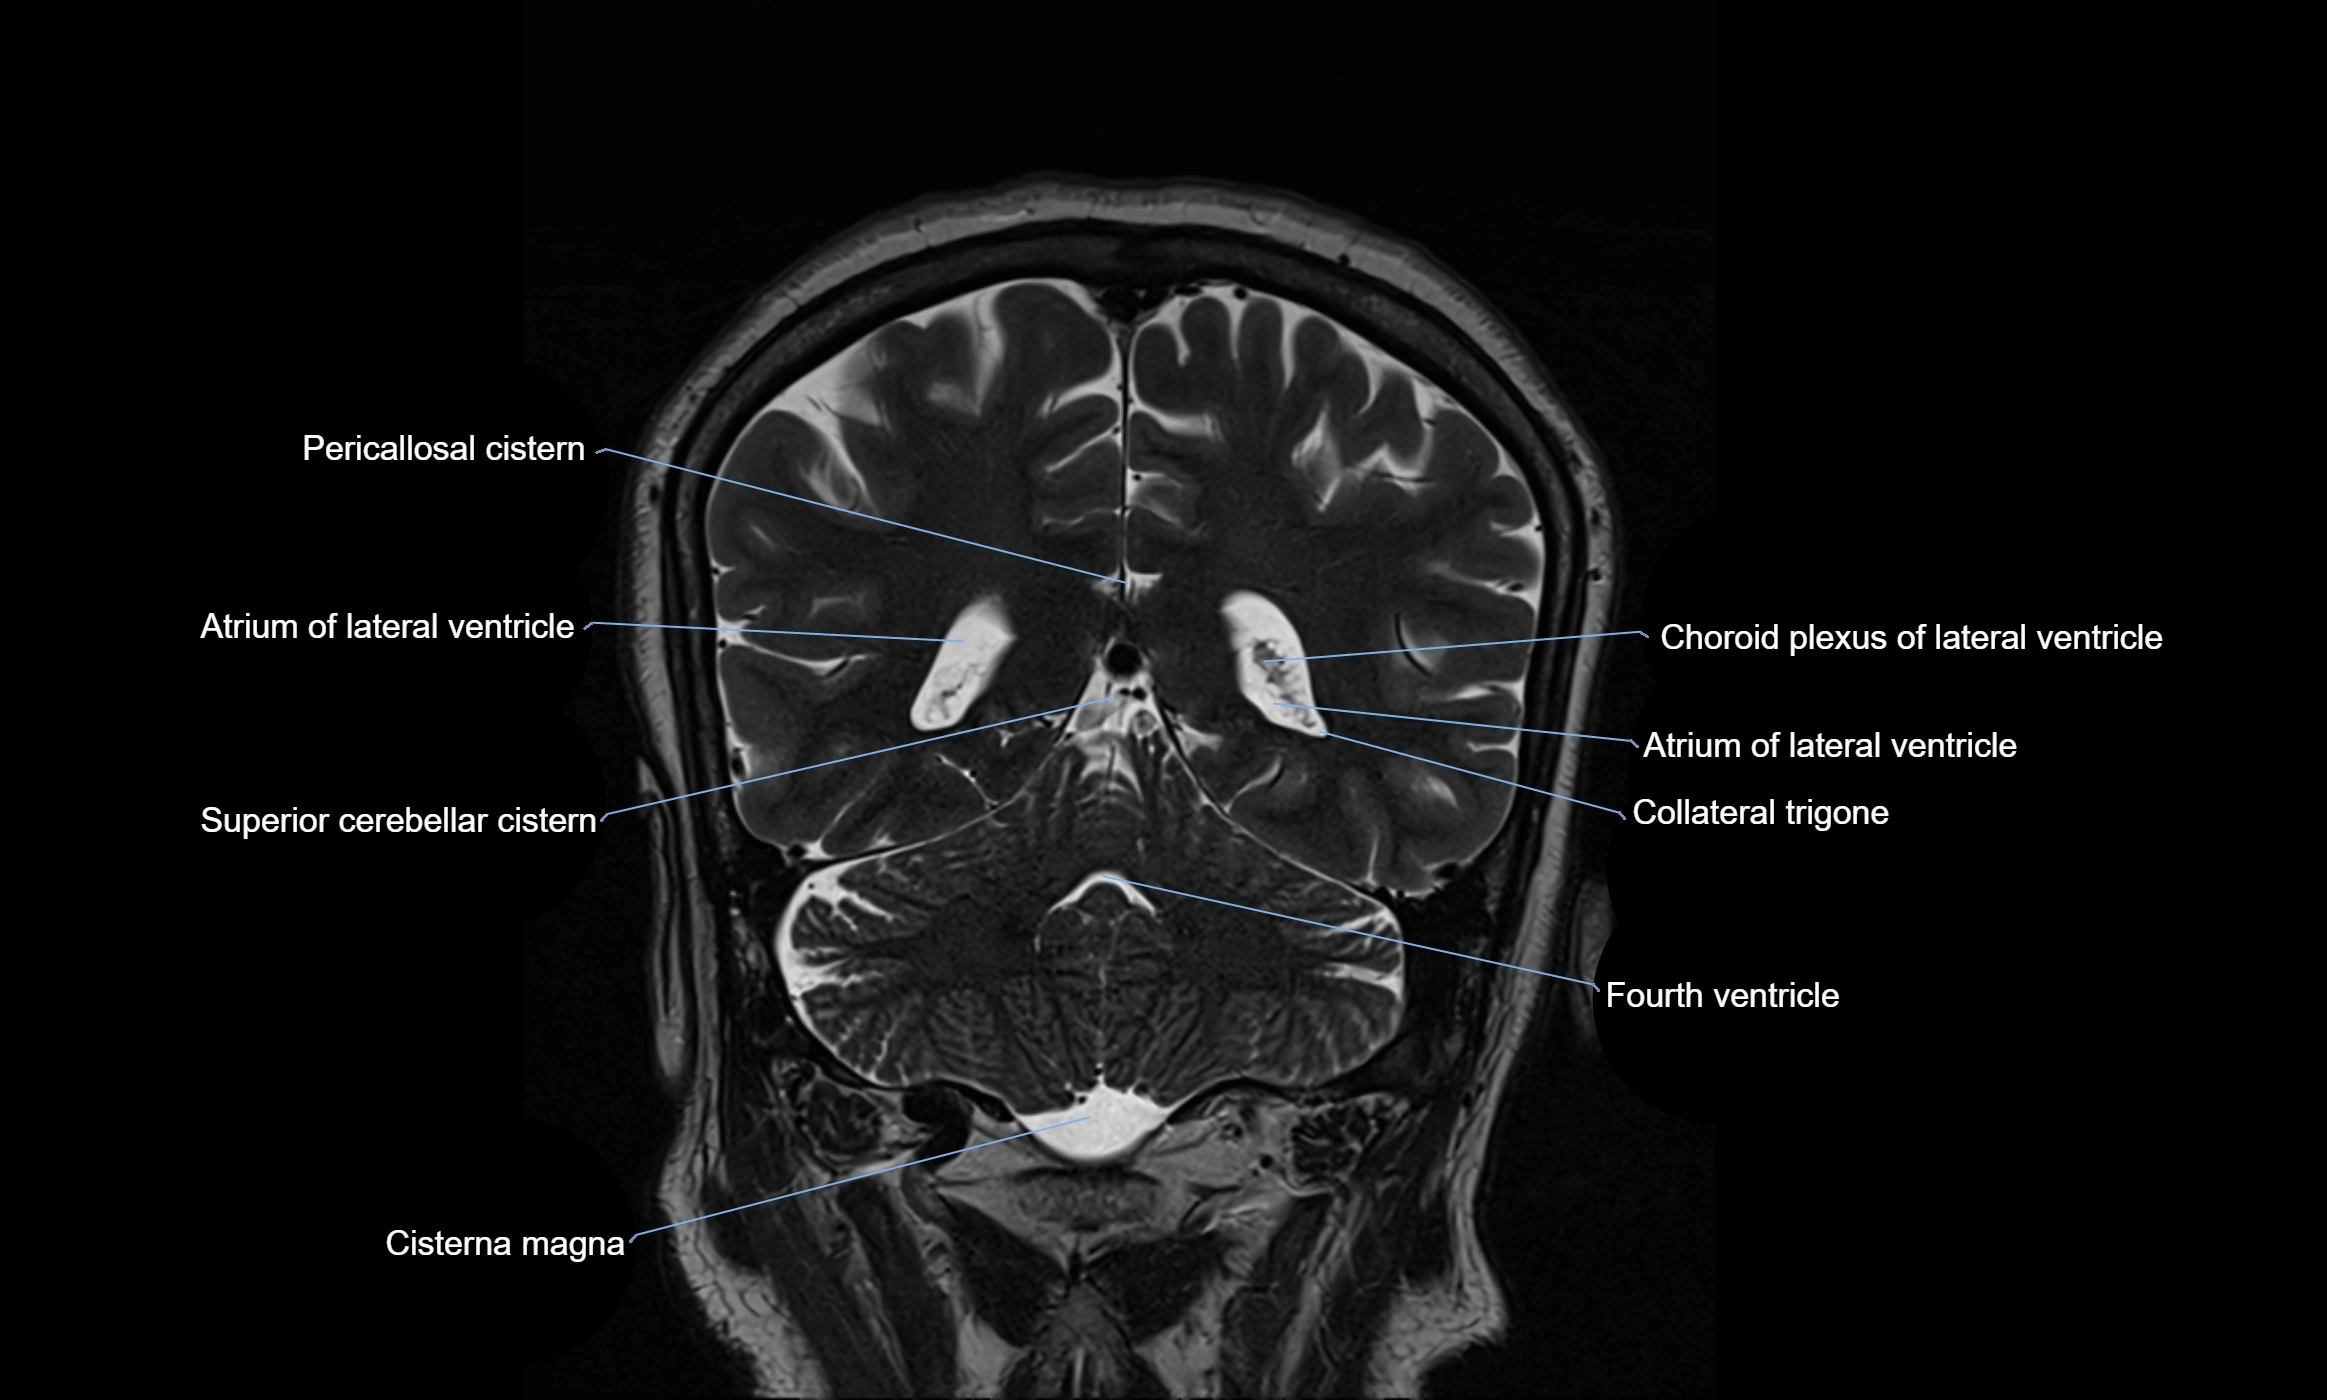

MRI images

image